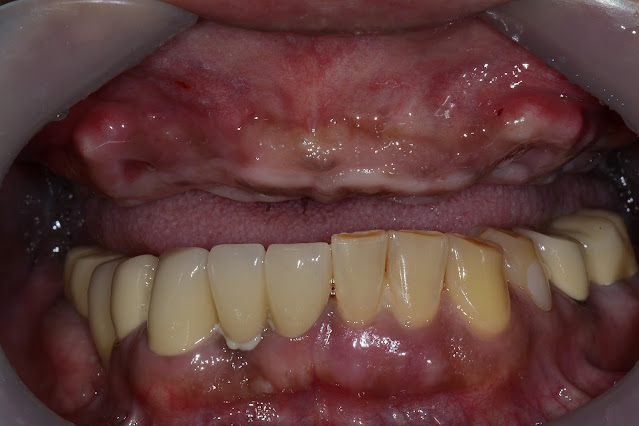

This is what it looks like after the second surgery.

The bone response is very good, all bone graft materials used were well maintained around the implant.

This is what it looks like after the final prosthetics. I am a little dissatisfied with the shape of the soft tissue in the upper central incisor area.The patient has no complaints at all. I decided to watch for a bit.